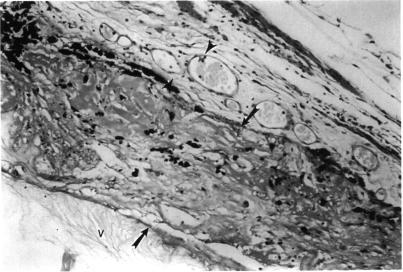

RESULTS

ANIMAL MODEL: Histopathologic examination of rabbit eyes treated with endocyclophotocoagulation demonstrated acute changes of ciliary process destruction, proteinaceous exudate, stromal edema, nuclear pyknosis, and pigment dispersion. Vascular congestion was seen with some hemorrhage. Later, replacement by fibrous or fibrovascular scar developed with loss of the pigmented and nonpigmented ciliary epithelia, absence of ciliary architectural elements, and pigment rounding and clumping. Human Eyes: Histopathologic examination of enucleated human eyes revealed total ablation of the ciliary processes with fibrosis and pigment clumping in areas of treatment. Abrupt transitions between treated and untreated regions could be identified. In some areas fibrocellular membrane proliferation was found extending over the scars that replaced the ciliary processes. Clinical series: Seventy-three patients were identified ranging in age from 2 to 85 years (mean, 57.7), with follow-up of 6 to 130 months (mean, 28.6). Mean number of previous operations was 3.5; mean number of previous glaucoma operations was 1.3. Preoperative mean IOP was 38 mmHg (range, 19 to 75), postoperative mean IOP was 16 mmHg (range, 1 to 50). At 6 months, 58 of 72 eyes (81%) with available IOP data had IOP greater than 5 mmHg and less than 22. At 12 months 48 of 55 (87.3%) were successfully controlled by these criteria, and at last follow-up 50 of 73 (68%). Fifty-six of 73 eyes (77%) were considered clinically stable at the last follow-up in terms of visual acuity, anatomic integrity, and IOP < or = 23 off all glaucoma medications. Visual acuity was stable or improved in 53 of 73 eyes (73%). Complications developed in 9 eyes (12%), including IOP < or = 6 mmHg in 6 eyes (8.2%), peripheral choroidal effusion in 4 (5.5%), fibrinous anterior chamber reaction in 3 (4.1%), phthisis in 2 (2.7%), and choroidal hemorrhage in 1. Thirty-five eyes had penetrating keratoplasty performed before or at the same time as endolaser (an average of 2.14 grafts each), Graft rejection occurred in 4 eyes (11%), and long-term failure of grafts occurred in 11 of 35 (31%). In 31 eyes, additional surgical procedures were performed at the time of endocyclophotocoagulation.

动物模型:经睫状体光凝术治疗的兔眼组织病理学检查显示睫状体破坏、蛋白质渗出、基质水肿、核固缩和色素弥散的急性变化。可见血管充血伴一些出血。之后,出现纤维或纤维血管瘢痕替代,色素性和非色素性睫状体上皮消失,睫状体结构成分缺失,色素聚集。人眼:摘除的人眼组织病理学检查显示睫状体完全消融,治疗区域有纤维化和色素聚集。可识别出治疗区域与未治疗区域之间的突然转变。在一些区域发现纤维细胞膜增生延伸至替代睫状体的瘢痕上。临床系列:共识别出73例患者,年龄2至85岁(平均57.7岁),随访6至130个月(平均28.6个月)。既往手术平均次数为3.5次;既往青光眼手术平均次数为1.3次。术前平均眼压为38 mmHg(范围19至75 mmHg),术后平均眼压为16 mmHg(范围1至50 mmHg)。在6个月时,72只可获得眼压数据的眼中,58只(81%)眼压高于5 mmHg且低于22 mmHg。在12个月时,55只眼中的48只(87.3%)按此标准眼压得到成功控制,在最后一次随访时,73只眼中的50只(68%)眼压得到控制。在最后一次随访时,73只眼中的56只(77%)在视力、解剖结构完整性及停用所有青光眼药物后眼压≤23 mmHg方面被认为临床稳定。73只眼中的53只(73%)视力稳定或提高。9只眼(12%)出现并发症,包括6只眼(8.2%)眼压≤6 mmHg,4只眼(5.5%)周边脉络膜积液,3只眼(4.1%)纤维素性前房反应,2只眼(2.7%)眼球痨,1只眼脉络膜出血。35只眼在激光睫状体光凝术前或同时进行了穿透性角膜移植术(平均每只眼2.14次移植),4只眼(11%)发生移植排斥,35只眼中11只(31%)移植长期失败。31只眼在激光睫状体光凝术时进行了额外的手术操作。